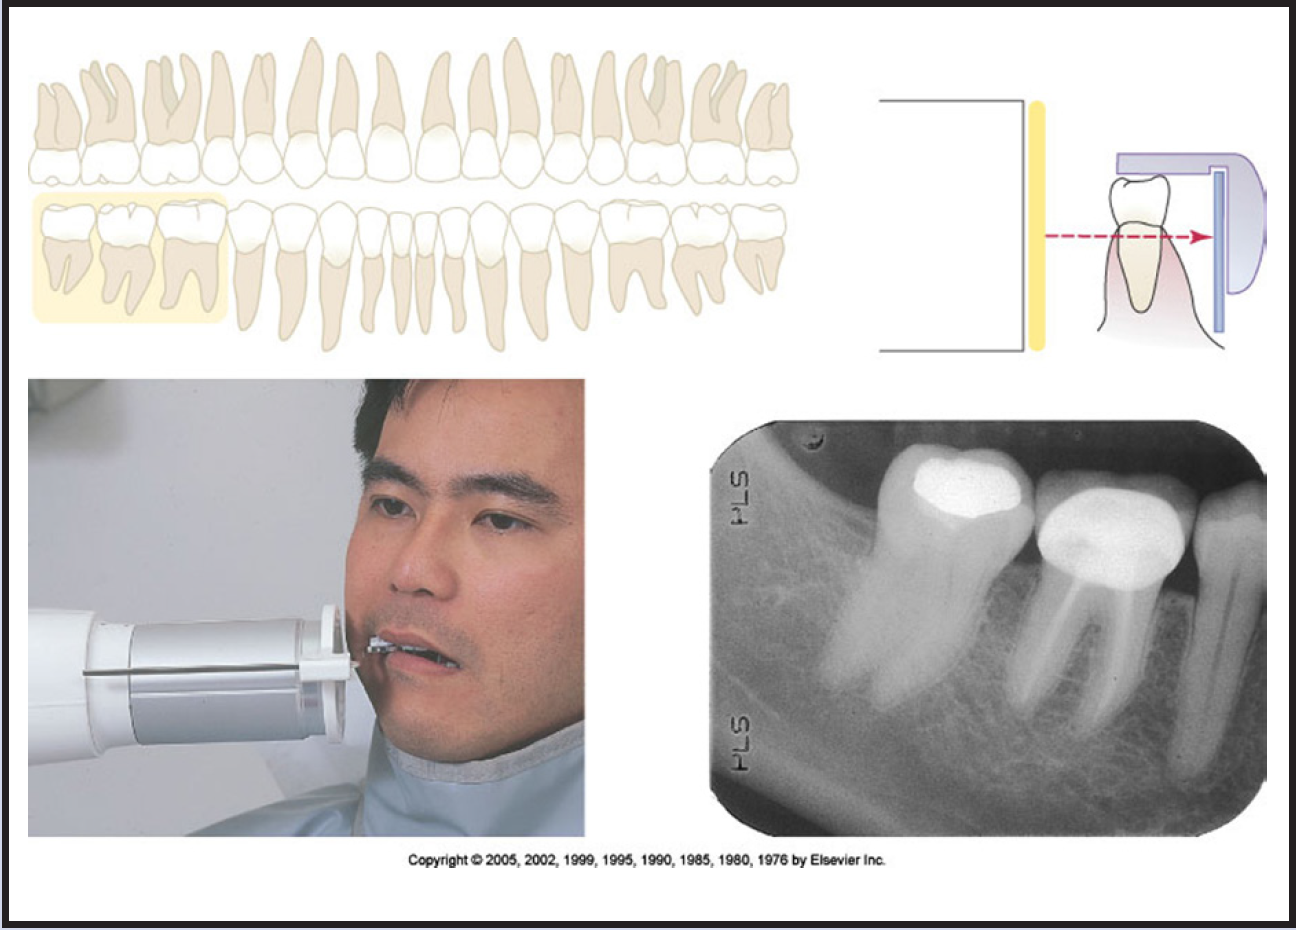

Bitewing images are parallel images because the receptor is positioned parallel to the long axis of the teeth and the beam is perpendicular to the receptor as in Figure 60. A bitewing tab is utilized to stabilize the receptor as the patient bites together.

Tube head position is illustrated in Figure 62, and a sample set of bitewing radiographic images is illustrated in Figure 63.

Figure 3 - Occlusal Images

Figure 3